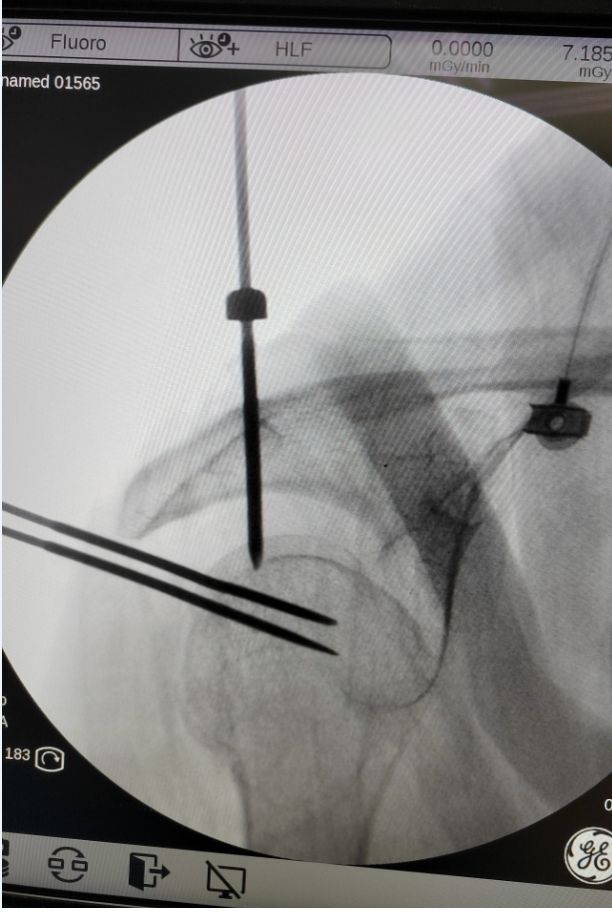

置入定位针

在充分考虑吕爷爷的病情和生活质量后,潘主任团队经过多次综合评估,认为手术治疗是目前较为适宜的选择。在与患者及家属进行深入沟通,详细告知该类骨折的特点、手术治疗方式的优点及预后情况后,获得了患者及家属的理解与同意。在吕爷爷身体状况良好的情况下,潘主任团队采用了微创治疗的方式,为吕爷爷顺利进行了闭合复位髓内钉内固定手术。